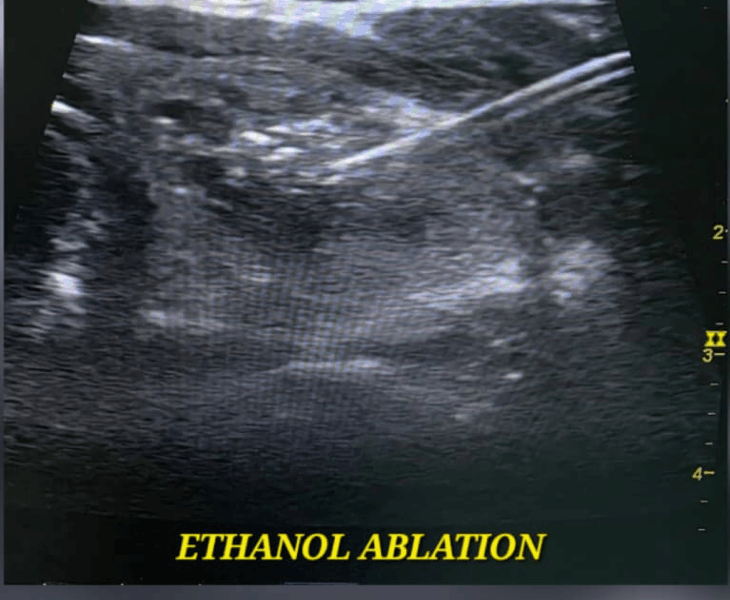

- Ethanol ablation: ethanol is injected into the cyst wall to stop re‑accumulation of fluid.

Follow‑up ultrasound typically shows reduction in size and reduced or absent vascularity within the nodule as it shrinks.